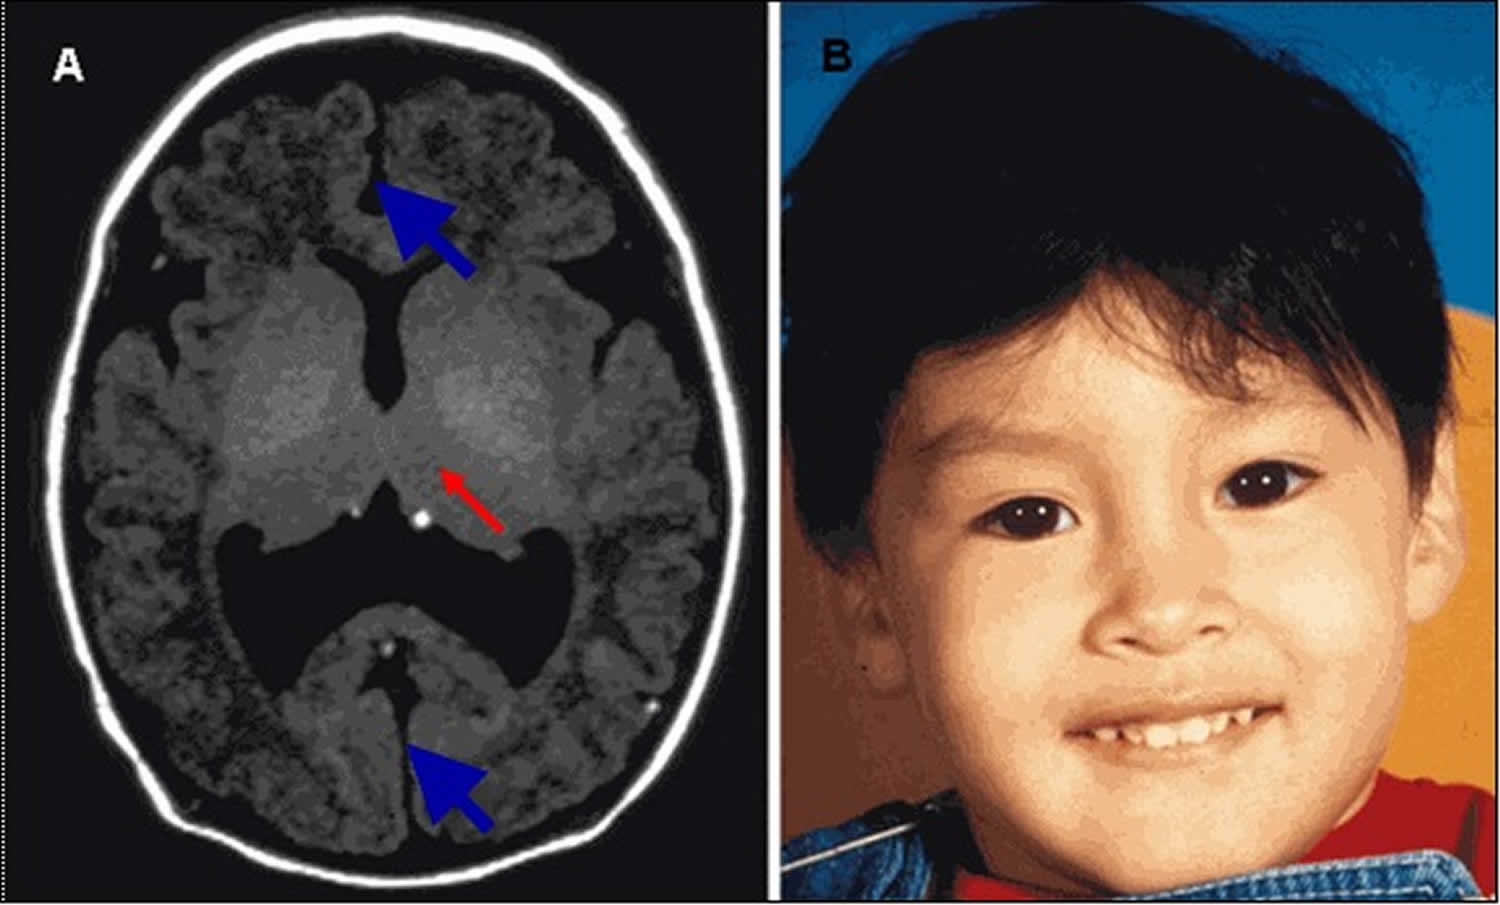

Congenital lobar emphysema | Radiology Case | Radiopaedia.org  Lobar holoprosencephaly | Radiology Case | Radiopaedia.org

Lobar holoprosencephaly | Radiology Case | Radiopaedia.org  Congenital lobar emphysema | Eurorad

Lobar TV - Lobar Incorporated  Lobar holoprosencephaly | Radiology Case | Radiopaedia.org

Lobar holoprosencephaly | Radiology Case | Radiopaedia.org  Congenital lobar emphysema | Image | Radiopaedia.org

Lobar holoprosencephaly | Radiology Case | Radiopaedia.org  Semilobar holoprosencephaly: 2D and 3D ultrasound

Lobar holoprosencephaly | Radiology Case | Radiopaedia.org  Lobar hemorrhage | Radiology Reference Article | Radiopaedia.org

Lobar holoprosencephaly | Radiology Case | Radiopaedia.org  About - Lobar Incorporated

Lobar holoprosencephaly | Radiology Case | Radiopaedia.org  Lobar holoprosencephaly | Radiology Case | Radiopaedia.org | Radiology, Case, Medical conditions

Lobar holoprosencephaly | Radiology Case | Radiopaedia.org | Radiology, Case, Medical conditions  39 Congenital Lobar Emphysema | Radiology Key

Holoprosencephaly causes, diagnosis, prognosis and treatment  Lal tisart dj song no voice tag ðððð - YouTube

A case of lobar holoprosencephaly in neonatus one-month old who | Download Scientific Diagram  Lobar holoprosencephaly | Image | Radiopaedia.org

Lobar holoprosencephaly | Image | Radiopaedia.org  Lobar Pneumonia at 10x Magnification | MicroscopyU

a: Lobar holoprosencephaly (HPE), ultrasound diagnosis at 15 weeks of | Download Scientific  Congenital lobar emphysema: diagnostic and therapeutic challenges | BMJ Case Reports

Lobar holoprosencephaly | Radiology Case | Radiopaedia.org